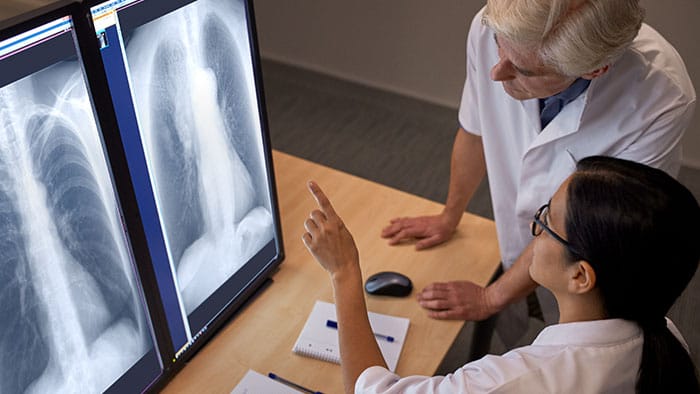

El equipamiento para rayos X y fluoroscopía de Philips ofrece un flujo de trabajo y una calidad de imágenes excelentes para impulsar el rendimiento y la precisión de diagnósticos, y garantiza un alto nivel de satisfacción para el personal y los pacientes. No existen límites para lo que podemos hacer juntos. Porque hoy la salud no tiene límites, y tampoco debería tenerlos la atención médica.

Mejoramos la experiencia del paciente en su paso por la atención médica

Vea cómo, luego de instalar la DigitalDiagnost C90, el equipo de la Physicians Clinic of Iowa (PCI) en Cedar Rapids disfruta de mayores capacidades en relación a los exámenes clínicos, una nueva optimización en los flujos de trabajo, exámenes más rápidos, y un nivel más alto de satisfacción para el personal y los paciente.